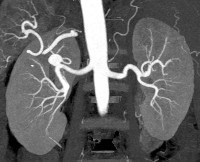

• Ангиография почечных артерий. Контрастное вещество, вводимое этим методом исследования, позволяет оценить сосудистую систему органа, определить местоположение аневризмы с большой точностью, ее тип, размер, подтвердить или отказаться от кровотечения. Почечная ангиография позволяет уточнить степень сужения, наличие тромбов, тромбоэмболии.